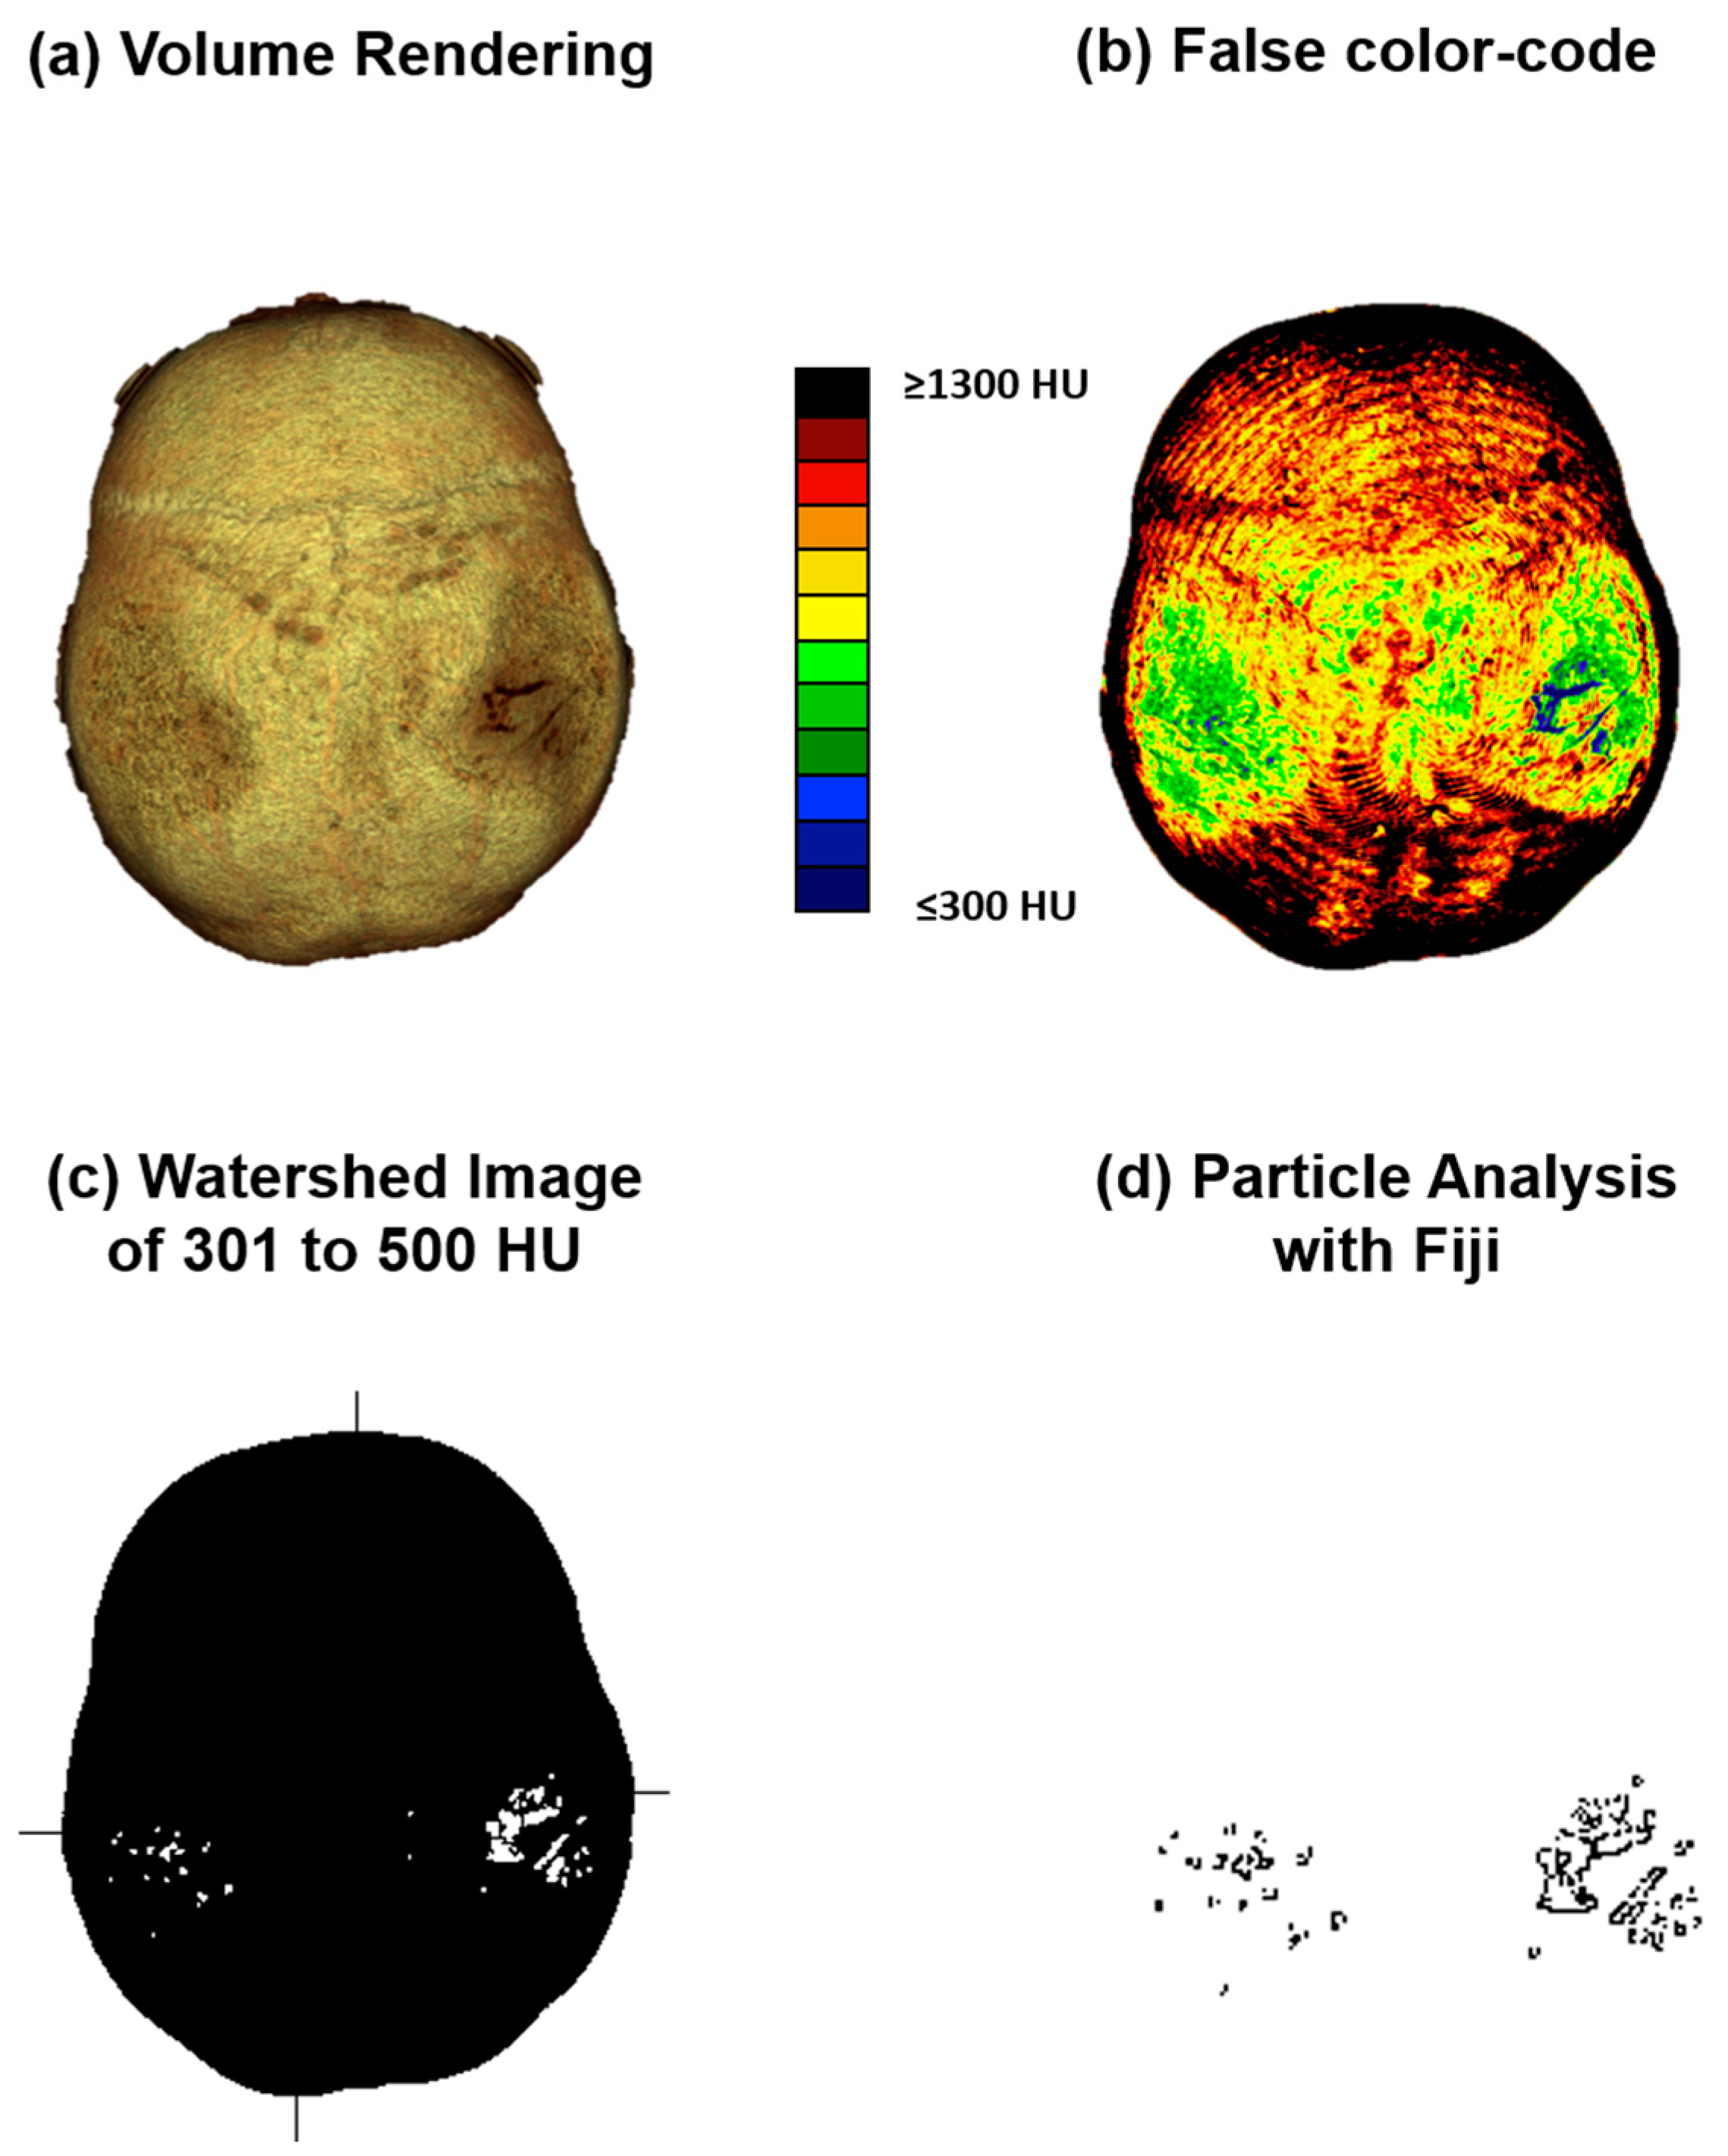

2.2.2. Computed Tomography Osteoabsorptiometry

2.2.3. Analysis of Densitogram Patterns

2.2.4. Three-Dimensional (3D) Measurement Method